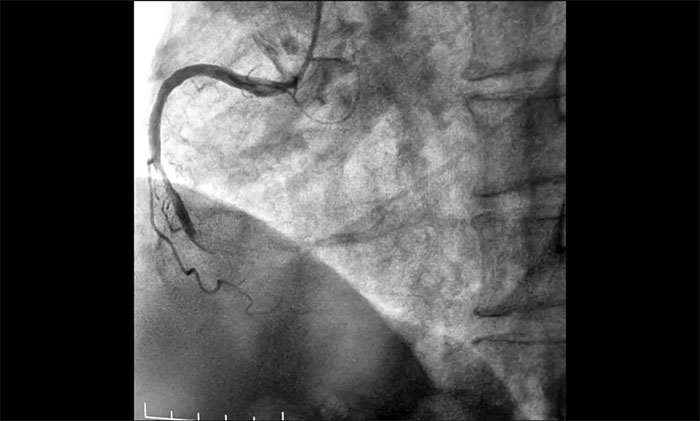

近日,上海蓝十字脑科医院为一名急性心梗患者实施介入手术。该患者因“间断心前区不适伴咽部束缚感7小时,全身乏力3小时”入院,综合其病史和相关检查确诊其为急性下壁心肌梗死,随时有猝死风险,手术指征明确。经球囊扩张和支架置入,开通闭塞血管,助其恢复心肌供血。

▲ 术前,前降支、回旋支、右冠状动脉严重狭窄及完全闭塞